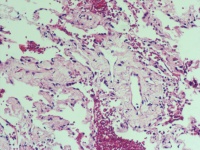

CT示左肺节段性肺不张 合并占位 既往有前列腺Ca病史

肺穿刺活检

0.5*0.3*0.2cm灰红碎组织

老师您好,这几个图片貌似没有恶性病变呀

慢性炎。